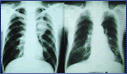

Ispitivanje disajne funkcije

Testovi kojima se ispituje disajna funkcija otkrivaju kako pluća u celini rade, ali mogu i da nas dovedu do tačnog mesta eventualnog poremećaja“, navodi za „Planetu“ pulmolog, profesor dr Predrag Rebić.

Disanje je sinonim za život, za postojanje. Udah je najubedljiviji znak života. Dugo se može živeti bez hrane, neko vreme i bez vode, ali bez vazduha ni nekoliko minuta. Osnovna uloga pluća – tog fascinantnog organa koji omogućava da dišemo, dakle da živimo, da postojimo – jeste snabdevanje organizma kiseonikom i oslobađanje od ugljendioksida. Mehanizam razmene respiracijskih gasova vrlo je složen pa otud i tako čudesno zanimljiva građa pluća. Profesor dr Predrag Rebić, šef Katedre pulmologije na Medicinskom fakultetu i specijalista u Institutu za plućne bolesti pri Kliničkom centru Srbije, opisuje pluća kao mali organ veličine - jednog ara! .